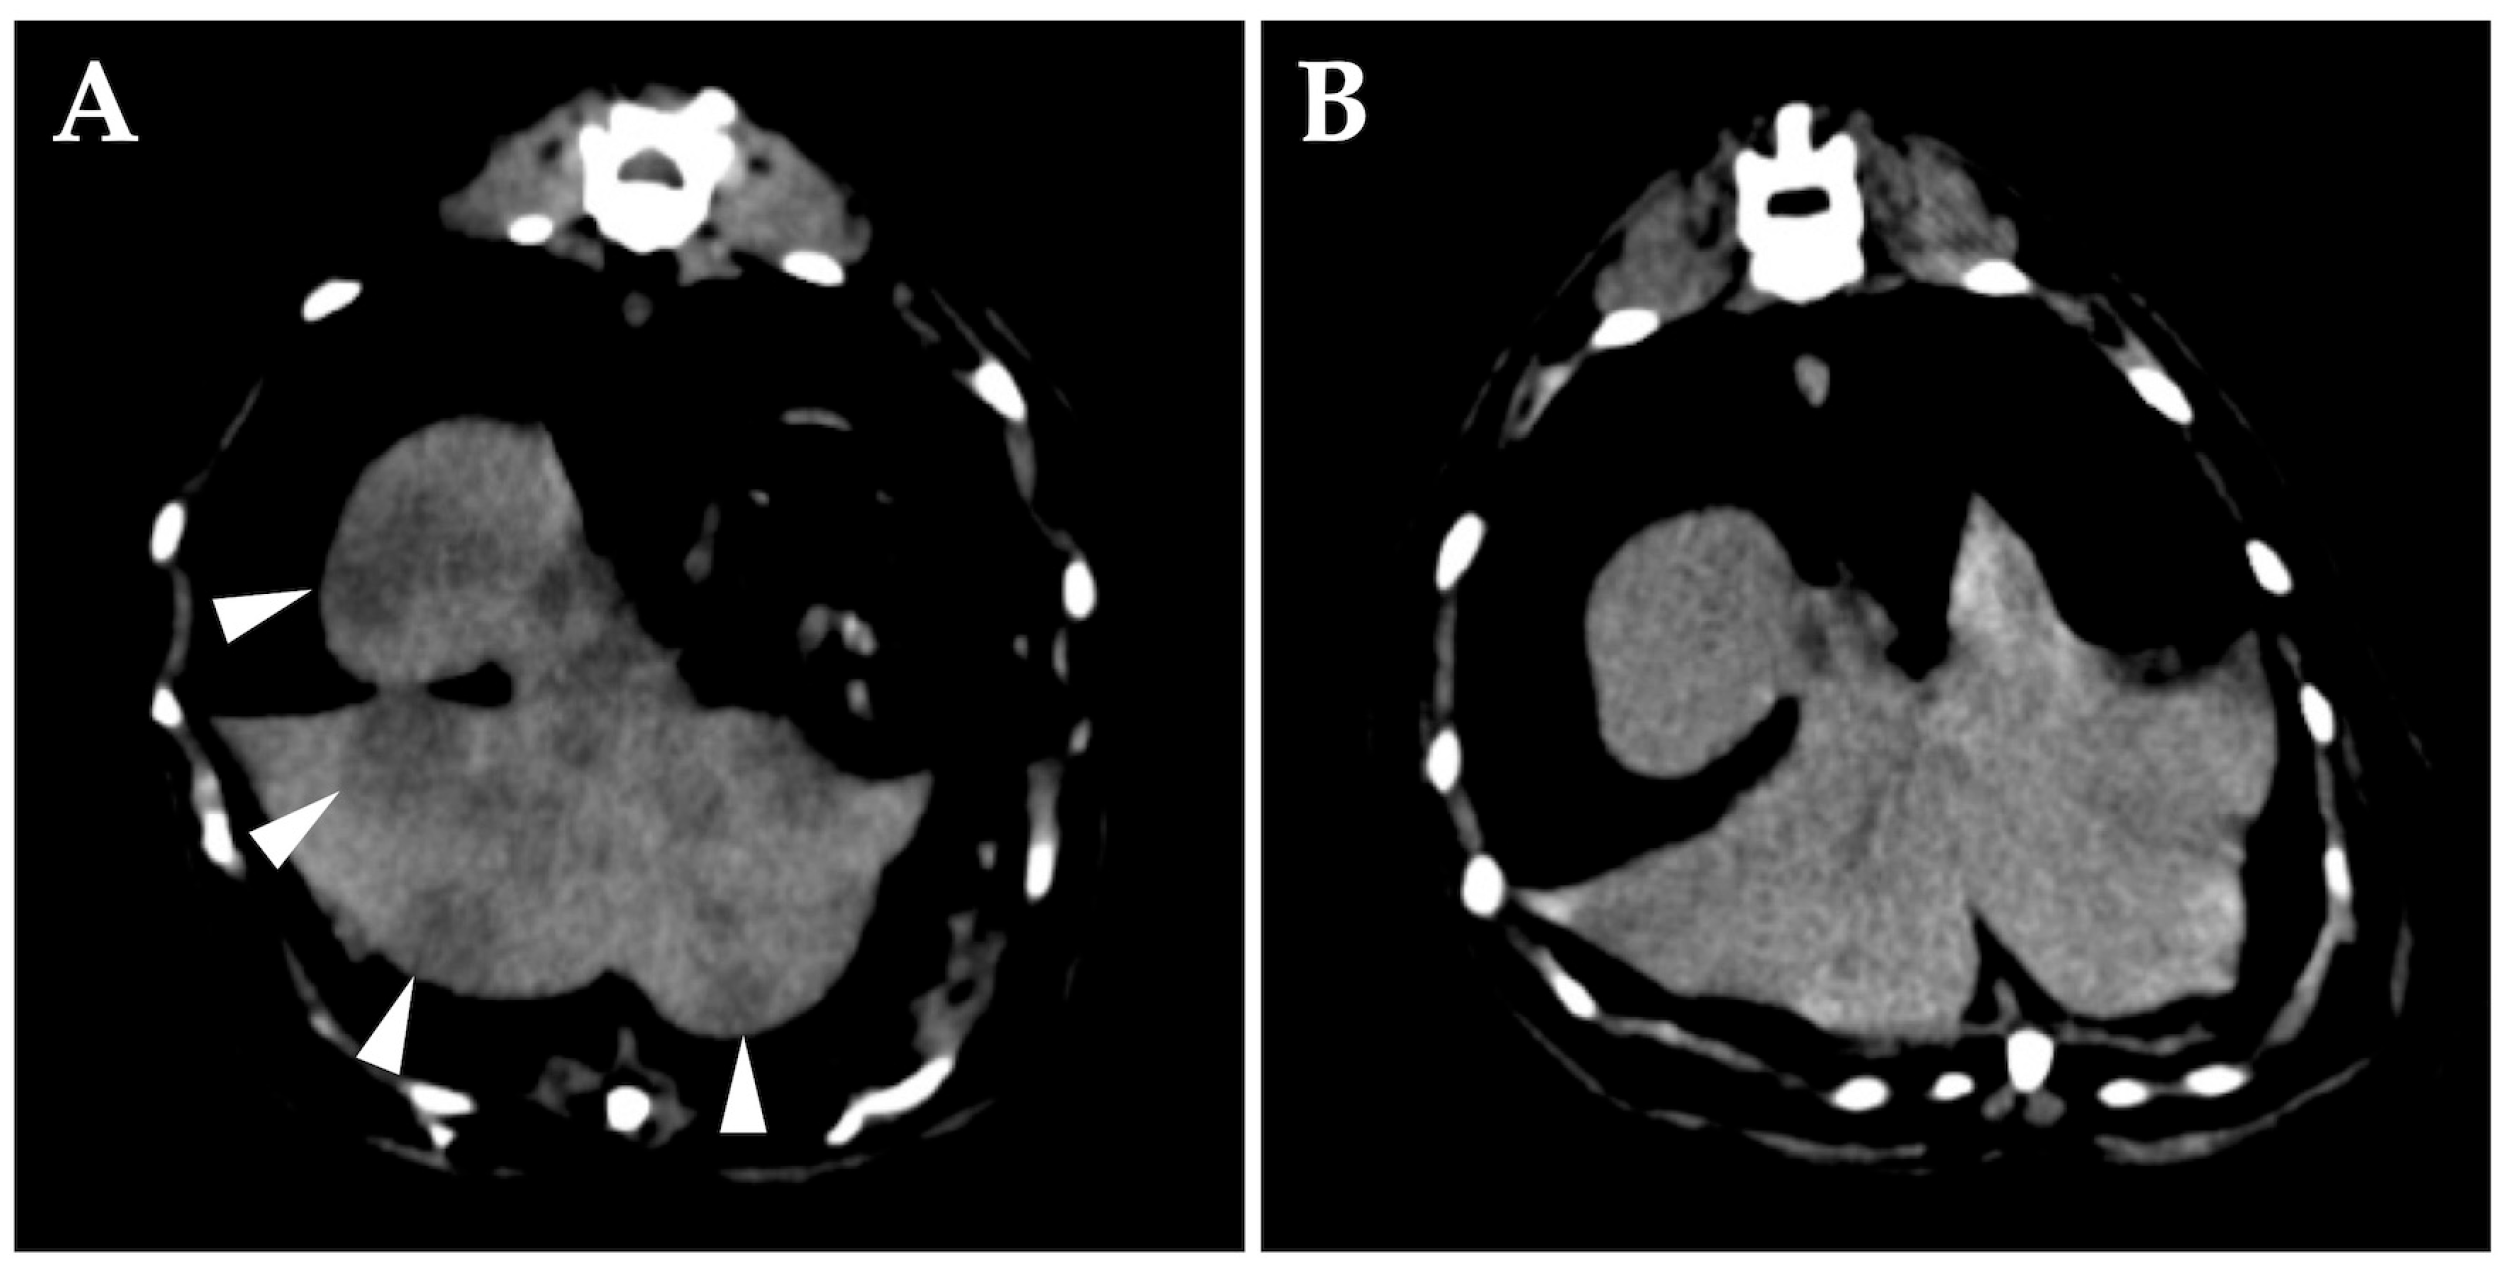

On day 42, whole-body CT without anesthesia or contrast media was performed for clinical staging. The middle ears appeared unchanged, but diffuse changes were observed in the liver (Figure 3A). Cytology of the liver lesions was not performed per the owner’s request. The tentative diagnosis was middle ear lymphoma with hepatic involvement, representing clinical stage 4 disease. After discussing the treatment plan with the owner, subcutaneous L-asparaginase was administered at 400 IU/kg (Kyowa Kirin, Tokyo, Japan). Prednisolone was continued at 5 mg/cat/day.

On day 56, right eyelid opening had improved. Follow-up whole-body CT without anesthesia or contrast media showed that the dorsolateral lesion of the right tympanic bulla had disappeared, the hepatic lesions were obscured (Figure 3B), and liver swelling had improved. L-asparaginase was evaluated as effective, and a second dose was administered.

Figure 3. Transverse computed tomography (CT) (without anesthesia or contrast media) of the abdomen at the level of the liver on day 42. (A) Numerous hypo-attenuating nodular lesions are seen in all lobes of the liver (arrowheads). (B) CT image of the same position on day 56. The hepatic lesions are obscured.